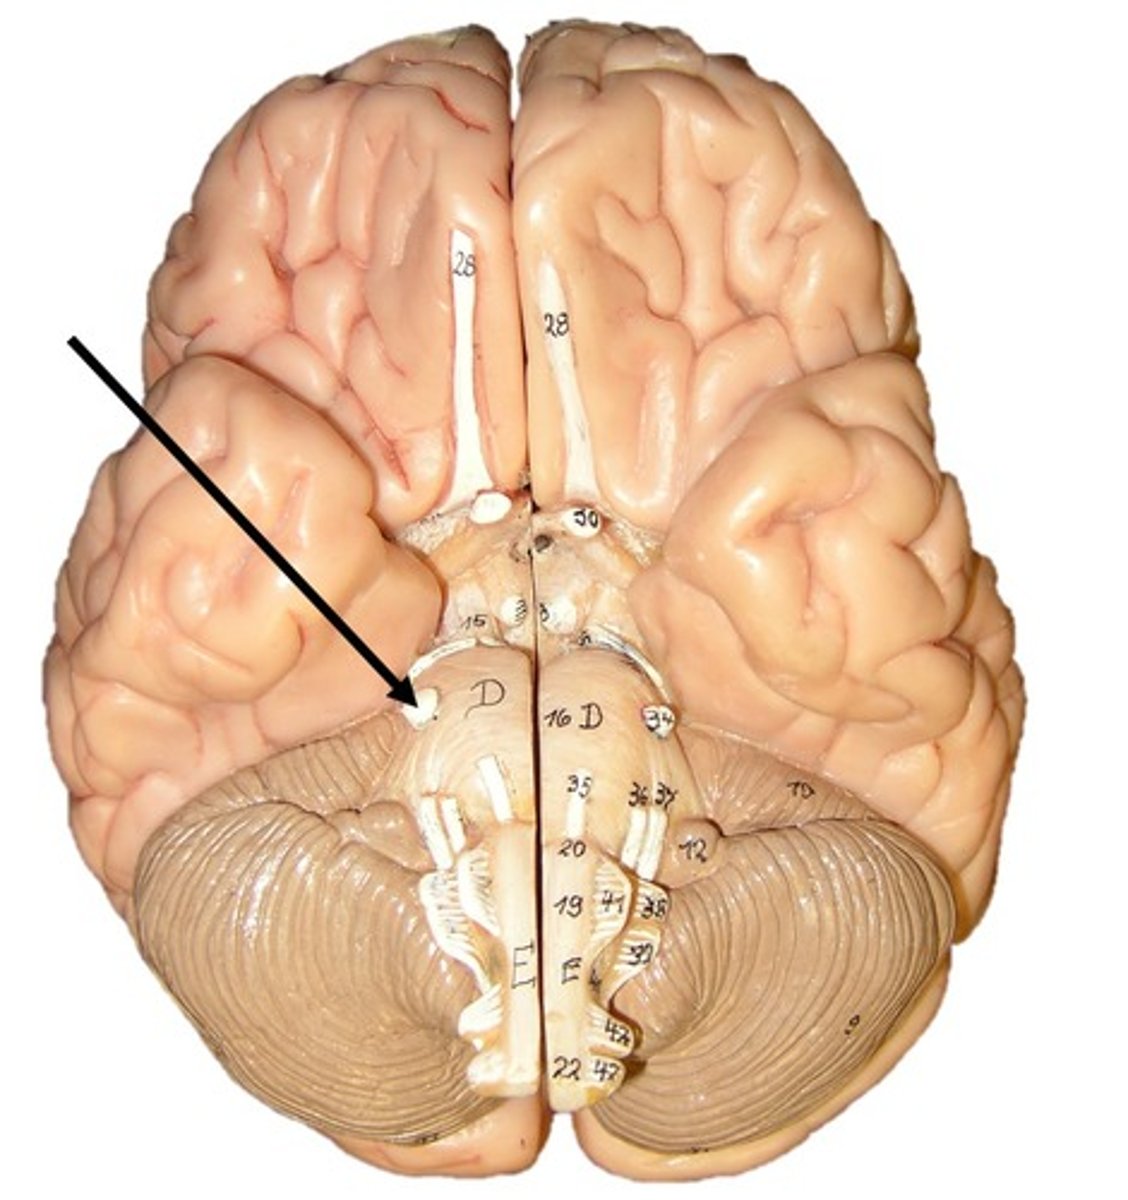

optic chiasm

Interthalamic adhesion

Thalamus

Medial geniculate nucleus

lateral geniculate nucleus

Hypothalamus

Mammillary body

Pituitary gland

Pineal gland

choroid plexus

lateral ventricles

cerebral aqueduct

third ventricle

fourth ventricle

pons

midbrain

medulla oblongata

olive

cerebral peduncles

optic tract

Amygdala